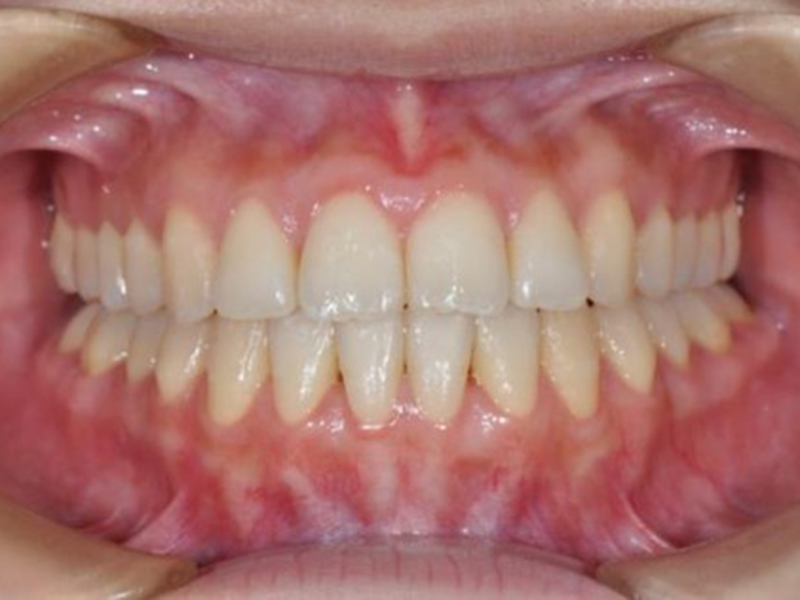

after